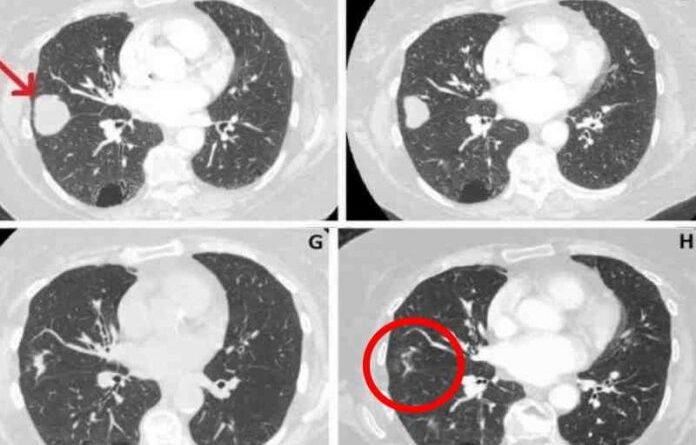

Após receber tratamento alternativo com canabidiol (CBD), o tumor no pulmão direito de uma idosa de 80 anos do Reino Unido reduziu em 76%.

O câncer foi descoberto em junho de 2018, com 41mm. Em março deste ano o tamanho era de 10mm.